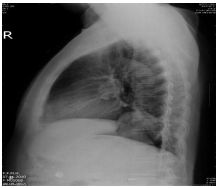

7.CC: cough for one year and back pain